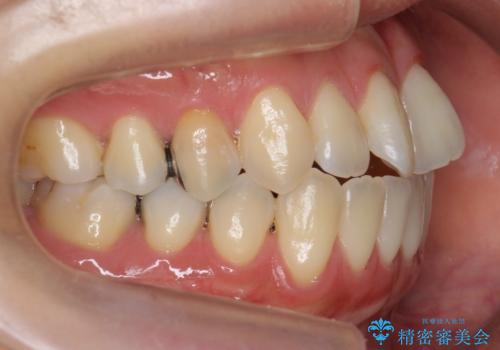

前歯のがたつき 若干受け口 インビザラインで

- 前歯のねじれおよび下の前歯が前に出ていることを気にして来院。

インビザラインで治療をおこないました。

前歯のねじれもなおり、比較的短期間でご満足いただけました。

部分矯正コースでしたので左下67の段差は特に治しておりません。

右下567及び左下6の虫歯治療も一緒に行っています。